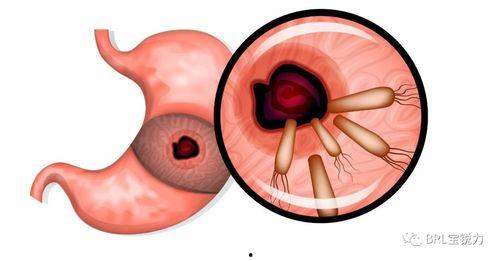

更严重的是,幽门螺旋杆菌还可能引发以下疾病:

1. 胃炎:幽门螺旋杆菌感染是慢性胃炎的主要病因。

2. 胃溃疡:幽门螺旋杆菌感染可能导致胃黏膜受损,形成溃疡。

3. 胃癌:长期感染幽门螺旋杆菌,可能导致胃癌的发生。